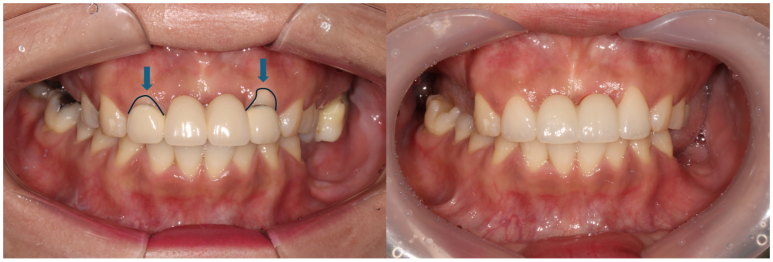

기다리는 동안 깔끔한 인상을 위하여 앞니 지르코니아 브릿지 치료를 해드렸어요.

왼쪽위 처음 내원하셨을 당시, 오른쪽이 앞니 지르코니아 완성 후 정면 사진입니다.

아직 어금니는 완성되지 않았지만..!...

보시면 파란색 화살표로 표시된 두 측절치에 기존에 치료받으셨던 PFM 브릿지의 경계가 드러나 회색 라인이 생기신 것을 보실 수 있고, 잇몸이 올라가버려 비교적 비 심미적인 모습인 것을 확인하실 수 있습니다.

지르코니아 브릿지로 교체함으로써 예쁜 첫인상을 완성해드렸어요.

이렇게 치료 중간에 환자분과 상의하면서 치아 색상을 적절히 채득해놓기에 가능한 일입니다.

본 환자분 같은 경우에는 자연스러운 치아 색상을 원하셔서 따뜻한 느낌의 색상으로 완성하였는데, 경우에 따라 보다 밝은 색상으로의 변화도 가능합니다! 연예인 라미네이트처럼요.

Before & After

좌측이 치료 전, 우측이 치료 후 정면 사진입니다.

솔직히 이제 치료를 받은 곳이 있으신가? 싶을 정도로 깔끔하게 마무리가 잘 된 것 같아요.

예쁜 앞니 지르코니아 크라운 제작은 저희 치과의 자랑입니다! 정말 색깔 잘 나왔네요~